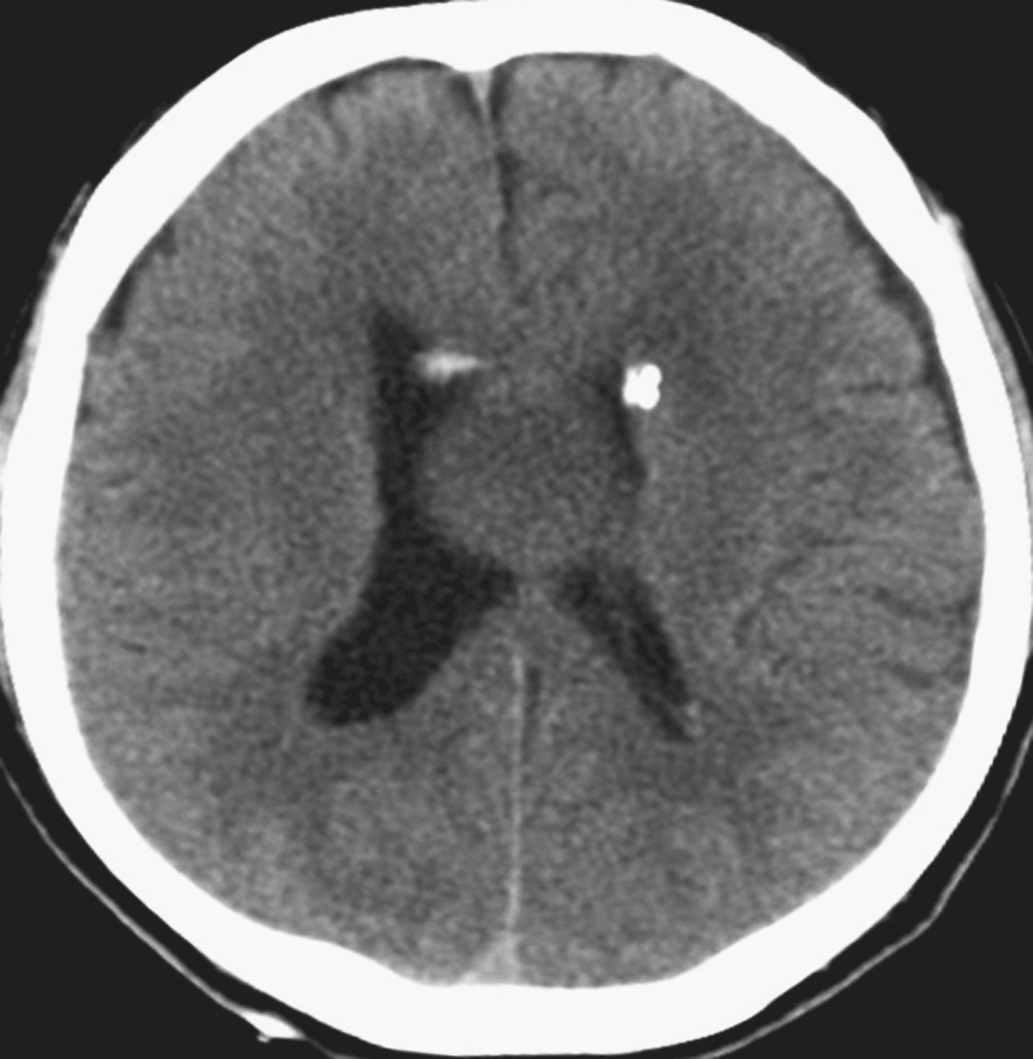

术后查体:神志恍惚,能简单回答问话。双瞳孔等大正圆,直径4.0mm,对光反射灵敏。颈软。四肢自主活动良好,肌张力略高。双侧Babinski征阴性。给予抗炎、脱水及对症治疗。术后24小时内复查头颅CT结果显示脑室系统明显变小(图5-1-4)。术后第3日患者神志清楚,问答合理。双侧脑室引流管通畅。术后第4日完善头颅MRI检查(图5-1-5)。双侧侧脑室外引流术后第6日于全身麻醉下行“经纵裂-胼胝体-穹窿间入路第三脑室内占位病变切除术”。手术过程顺利,复查头颅CT显示完全切除肿瘤,脑室大小基本正常(图5-1-6)。病理检查结果回报:胶样囊肿。患者2周后出院。目前随访恢复良好,未见肿瘤和脑积水复发。

图5-1-4 脑室外引流术后CT表现(引流术后24小时)

图5-1-6 肿瘤切除术后CT表现